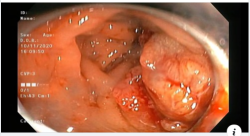

Sử dụng công nghệ NBI để nội soi, bác L đã phát hiện đại tràng trái có 01 polyp kích thước 2.5 cm, cuống dài. Ngay lúc đó, ê-kíp nội soi tiến hành thủ thuật thắt chân polyp và cắt polyp qua nội soi. Đồng thời, lấy polyp đã cắt làm giải phẫu bệnh. Trực tràng có 01 polyp kích thước 3 mm đã được bấm trọn bằng kìm sinh thiết.